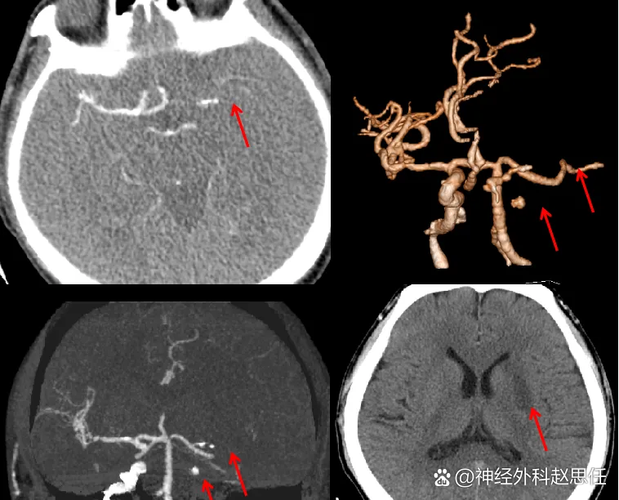

(图片来源网络,侵删)

(图片来源网络,侵删)- 方法:通过手臂的静脉注射一种叫“阿替普酶”(rt-PA)的溶栓药物,像“化血符”一样,将血栓溶解,恢复血流。